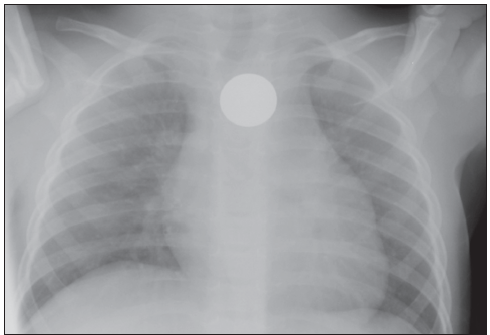

Infants and toddlers will put just about anything into their mouths.